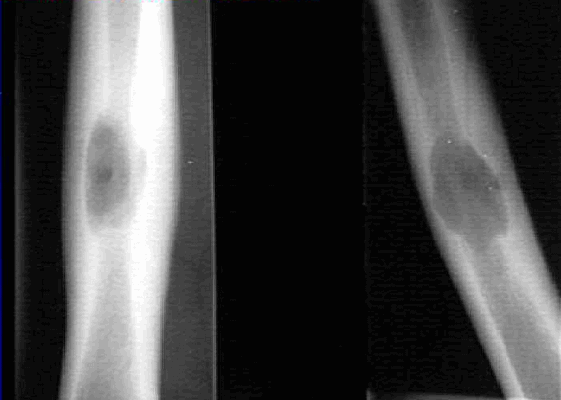

На рентгеновских снимках эозинофильная гранулема имеет вид литического очага округлой или овальной формы с четкими границами, расположенного преимущественно в костномозговой полости. При этом его размеры могут варьироваться в широких пределах. Как правило, признаки перифокального склероза отсутствуют. При поражении губчатой кости наблюдается так называемый пробойниковый дефект, а при локализации в позвоночнике может наблюдаться клиновидная деформация или формирование плоского позвонка. Таким образом, рентгенологическая картина при эозинофильной гранулеме не имеет специфических черт и во многом схожа с саркомой Юинга, остеогенной саркомой и другими злокачественными образованиями.

- Рентгенография костей. При рентгенологическом исследовании определяются единичные или множественные опухолевидные образования, участки деструкции, которые могут располагаться как в трубчатых, так и в плоских костях. При подозрении на эозинофильную гранулему обязательно проводят рентгенографию челюстей.